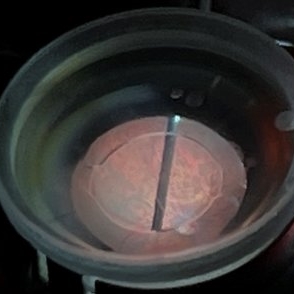

Direct lens, indirect vision.

Direct lens, indirect vision.

May 19 2022 by ALLAN GOMES DA SILVA

External view of vitrectomy under direct macular lens.

Photographer: Allan Gomes da Silva

Imaging device: Wide-angle camera - 26mm; f1.5; ISO 64; 208mm; 1/120 sec

Condition/keywords: retina surgery, vitreomacular surgery